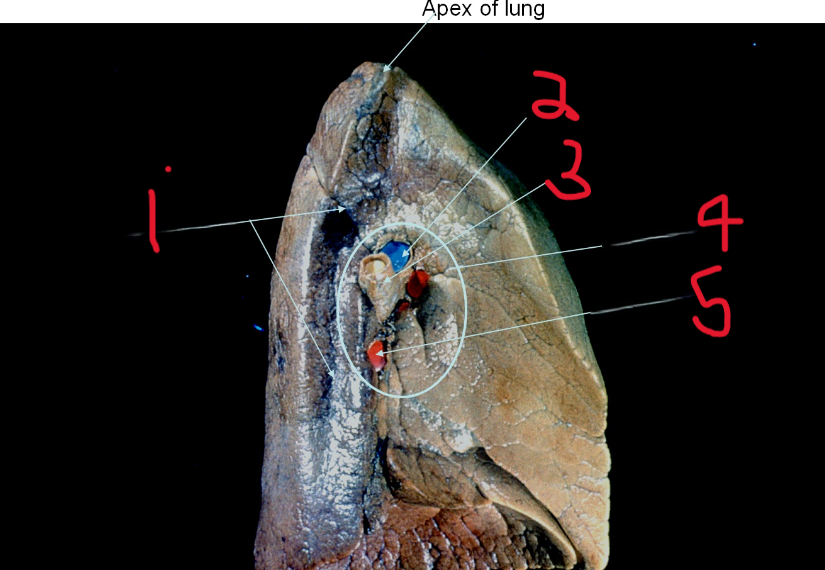

What is depicted by #1

Pulmonary artery

What is depicted by #2

Left main bronchus

What is depicted by #3

Hilum of lung

What is depicted by #4

Pulmonary vein

What is depicted by #5